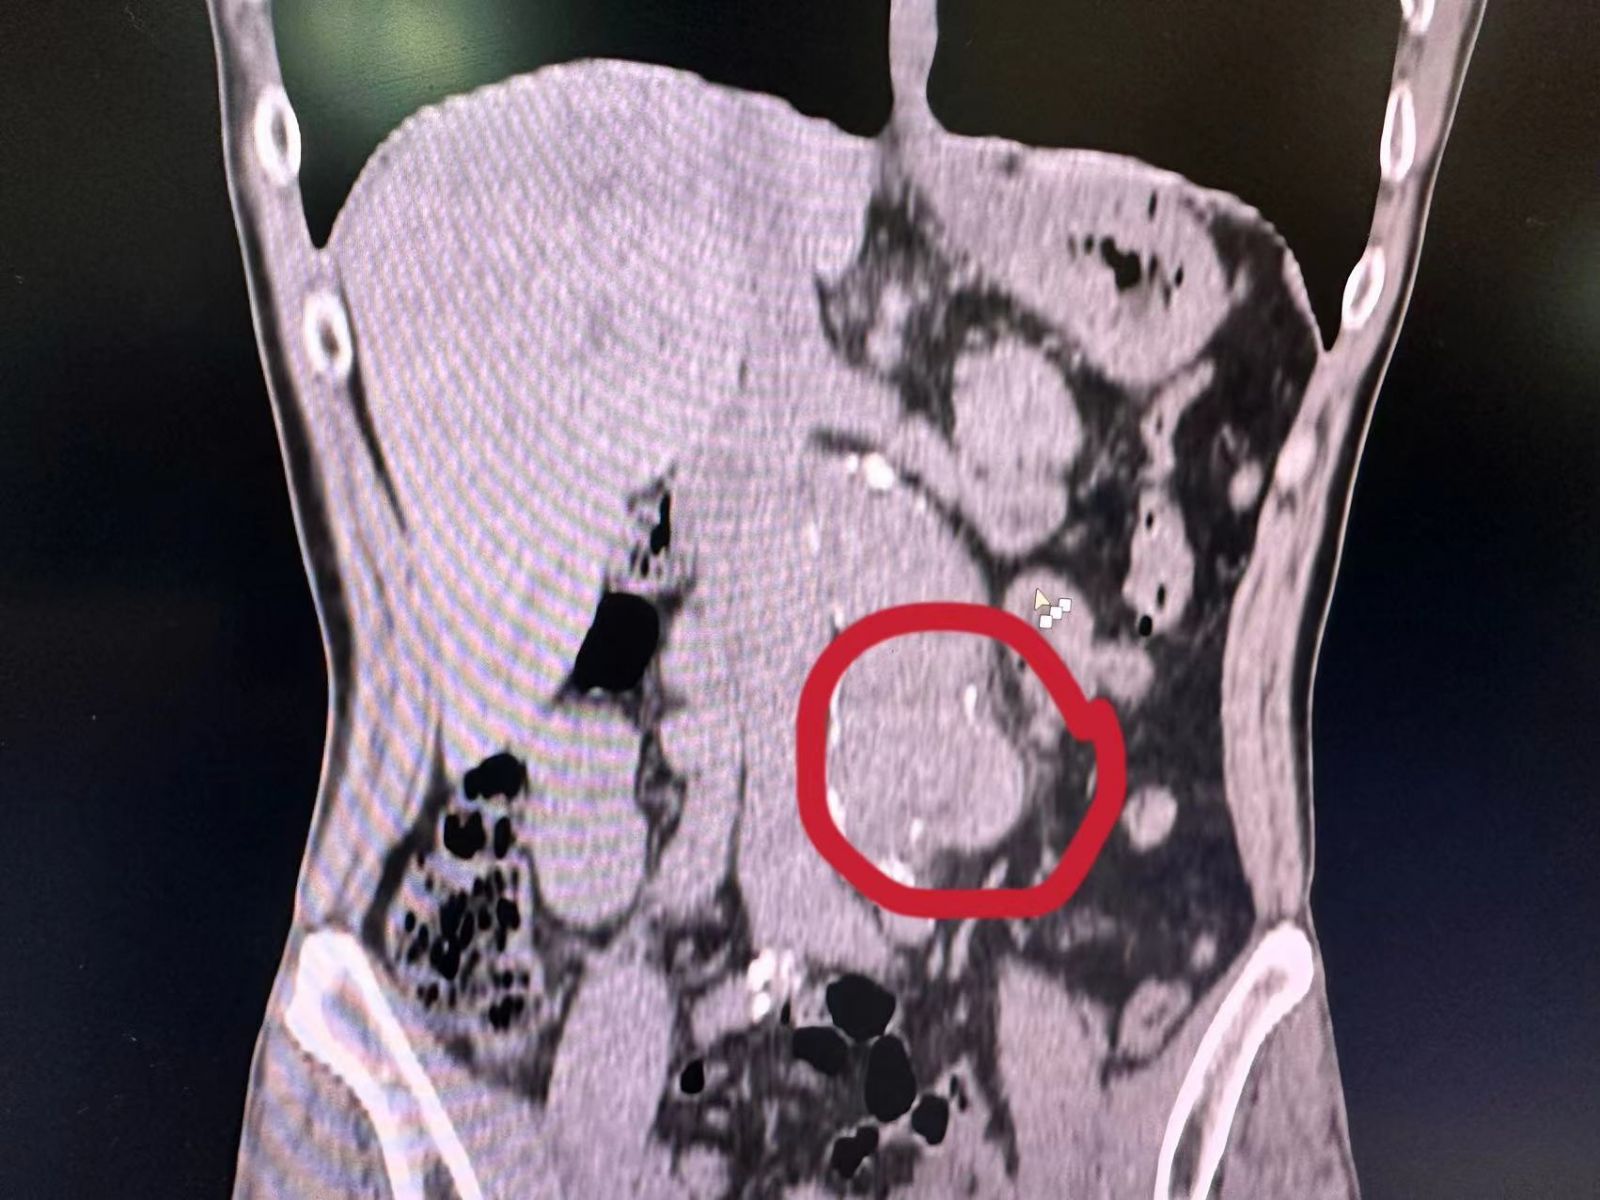

近日,一次常规门诊CT检查,在潘先生身上照出惊人一幕:腹主动脉瘤,腹主动脉壁上赫然膨出一个“定时炸弹”!这颗随时可能破裂的“炸弹”,让平静的门诊瞬间涌起紧张暗流。

腹主动脉瘤素来凶险,瘤体一旦破裂,九成患者抢救不及,生命将如风中残烛,片刻即灭。发现腹主动脉瘤必须立即转往具备血管外科手术能力的上级医院,生命通道刻不容缓。